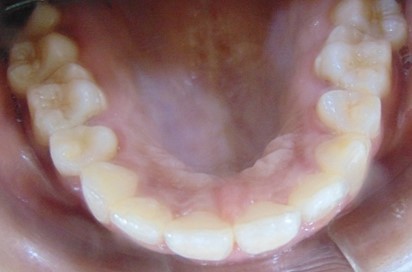

Divya Patil, 28Y, Duration - 6Months

Before

After

Image 2